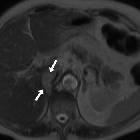

Isolated

intracaval recurrence of resected renal carcinoma. Portal venous phase images (a, b): sizeable, faint filling defect (arrows) in the intrahepatic inferior vena cava. Note metallic clips from previous radical nephrectomy without local recurrence in the surgical bed or adenopathies.

intracaval recurrence of resected renal carcinoma. Portal venous phase images (a, b): sizeable, faint filling defect (arrows) in the intrahepatic inferior vena cava.